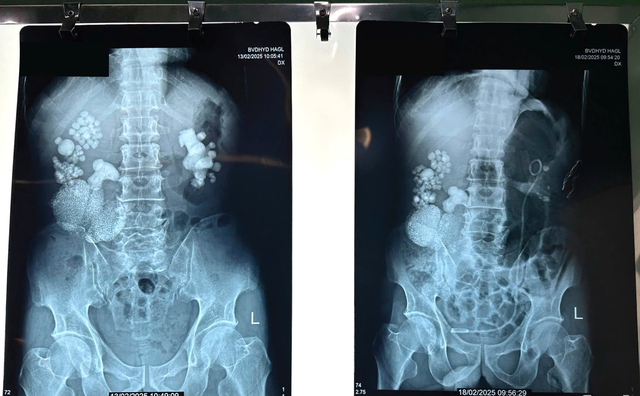

Hình ảnh chụp Xquang của ông C. Ảnh: BV. Đại học Y Dược-Hoàng Anh Gia Lai cung cấp.

Kết quả chụp CT, Xquang cho thấy, thận phải của người bệnh có kích thước lớn (163x80mm), ứ nước độ II-III, chứa nhiều sỏi tạo thành đám, kích thước 26x56 mm, trong đó có viên sỏi lớn tại khúc nối bể thận-niệu quản kích thước 31x32 mm.

Đặc biệt, người bệnh có khối tổn thương choán chỗ ở 1/3 giữa thận phải, nghi ngờ là bướu thận. Sau khi hội chẩn, các bác sĩ quyết định tiến hành phẫu thuật nội soi cắt thận, cùng với đó là lấy sỏi thận cho người đàn ông này.

Nhận định đây là một ca phẫu thuật khá phức tạp do số lượng sỏi nhiều, nhiều viên có kích thước lớn và có khối bướu thận kèm theo, nên yêu cầu thực hiện với độ chính xác cao. Ngoài ra, bệnh nhân đã cao tuổi nên có nhiều nguy cơ có thể xảy ra trong ca mổ.